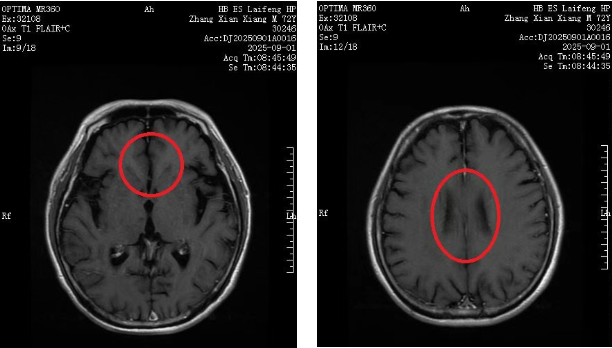

可谁也没料到,今年6月,化疗结束仅两个月,张大爷突然频繁头晕头痛、行走不稳,需要借助拐杖才能勉强活动。家人急忙再次送他到我院就诊,头颅核磁共振结果出来的那一刻,所有人的心又沉了下去:颅内多发转移,病情出现恶化!

就在全家陷入绝望之际,正在我院对口帮扶的湖北省肿瘤医院专家黄青教授详细翻看了张大爷既往接近100多页的病历,反复对比历次影像资料,同时通过远程会诊的方式与另外两名帮扶专家张曲和张平平教授交换治疗意见。最终,结合张大爷的身体状况,黄教授为他制定了新的 “靶向药物+化学治疗” 的个性化方案,还特意叮嘱肿瘤科医护团队:“老人年纪大,要多关注他的情绪变化和药物不良反应!”

经过3个周期的治疗,终于,最近一次复查显示,张大爷颅内的转移病灶基本消失,头晕、行走不稳的症状也完全缓解,已经完全脱离了拐杖,活动自如,连家属都称赞道: “这是超出预期的好疗效!”出院当天,张大爷与其家属特地送来锦旗表示感谢。